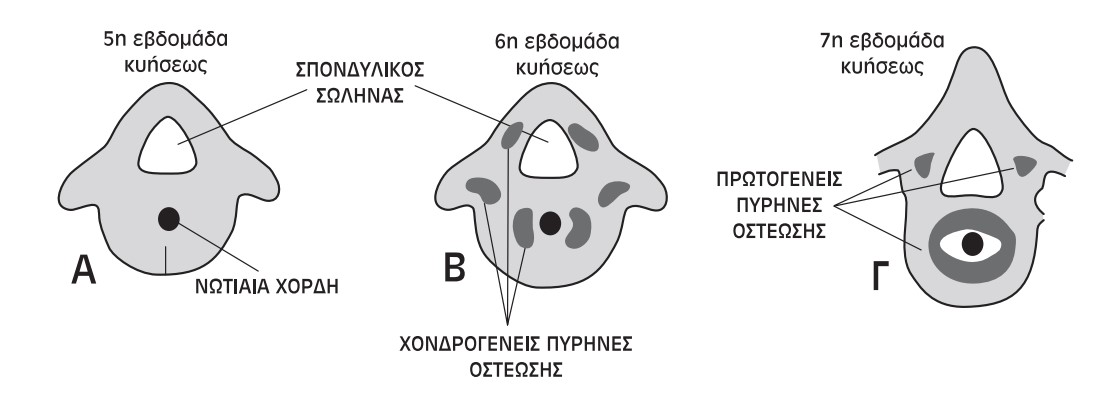

Από εμβρυολογική άποψη, οι σπονδυλικές ανωμαλίες επισυμβαίνουν κατά την 5η έως την 8η εβδομάδα της κύησης.

Εικόνα 8

Σε αυτή την περίοδο διαμορφώνονται οι ιστολογικές καταβολές των σπονδύλων από συναθροίσεις των σκληροτομιακών κυττάρων γύρω από τη νωτιαία χορδή.

Αυτοί οι μεσεγχυματικοί σπόνδυλοι τις επόμενες εβδομάδες διαχωρίζονται μεταξύ τους με την παρεμβολή του αρχέγονου μεσοσπονδυλίου δίσκου. Κατόπιν αναπτύσσονται οι πρωτογενείς πυρήνες οστέωσης, από όπου και σχηματίζονται οι οστέϊνοι σπόνδυλοι. Έτσι, είναι δυνατόν να έχουμε είτε μερική αποτυχία διαστηματοποίησης είτε μερική αποτυχία σχηματισμού ενός ή περισσότερων σπονδύλων.